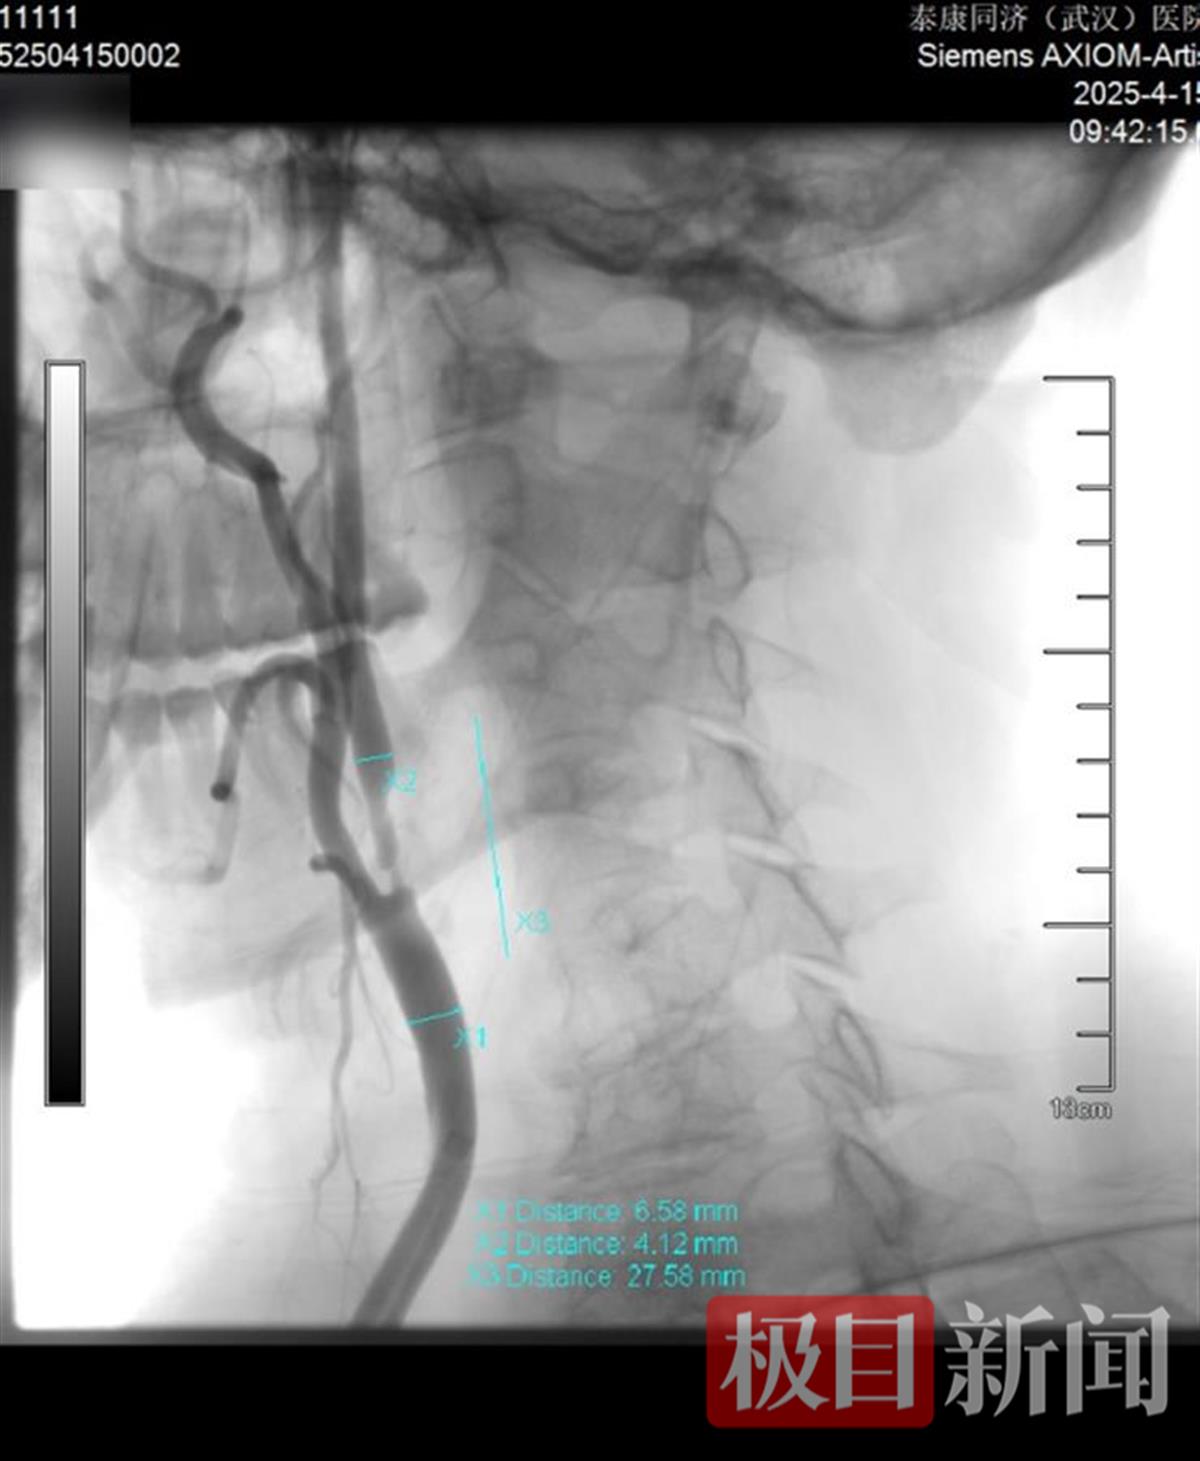

颈内动脉术前VS术后

近日,张庭保教授团队为患者实施“右侧颈内动脉球囊扩张术+支架植入术+左侧椎动脉药物球囊支架置入术”。术后脑血管造影显示,右侧颈内动脉及左椎动脉狭窄情况明显改善。患者术后恢复良好,目前已康复出院。